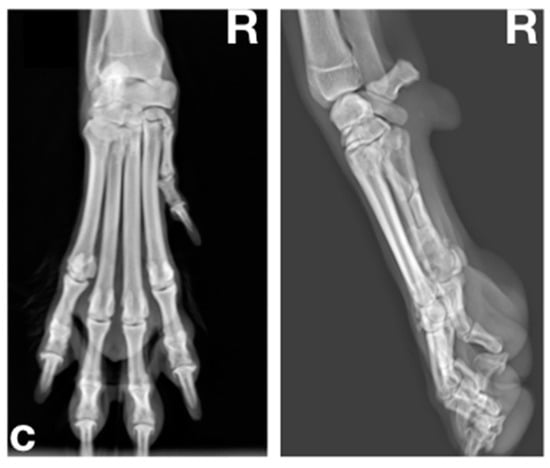

2.3.2. Radiographic Examination